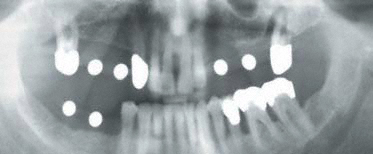

Für ein Implantat werden sowohl eine Mindest-Knochentiefe als auch ein Sicherheitsabstand im Unterkiefer zum Nervenkanal vorausgesetzt. Die Knochentiefe wird durch spezielle Röntgendiagnostik ermittelt.

Die reale Knochenhöhe wird mit Hilfe einer Tiefziehschiene mit eingearbeiteten Metallkugeln ermittelt. Bei digitalen Röntgengeräten kann gegebenenfalls auf die Messaufnahmen verzichtet werden, da sie über ein integriertes Messtool verfügen. Zur Detailabklärung kann es erforderlich sein, zusätzliche Aufnahmen von einzelnen Zahnabschnitten zu machen.

Durch die Computertomographie kann die Lage der später zu setzenden Implantate im Vorfeld schon auf den Millimeter bestimmt werden.